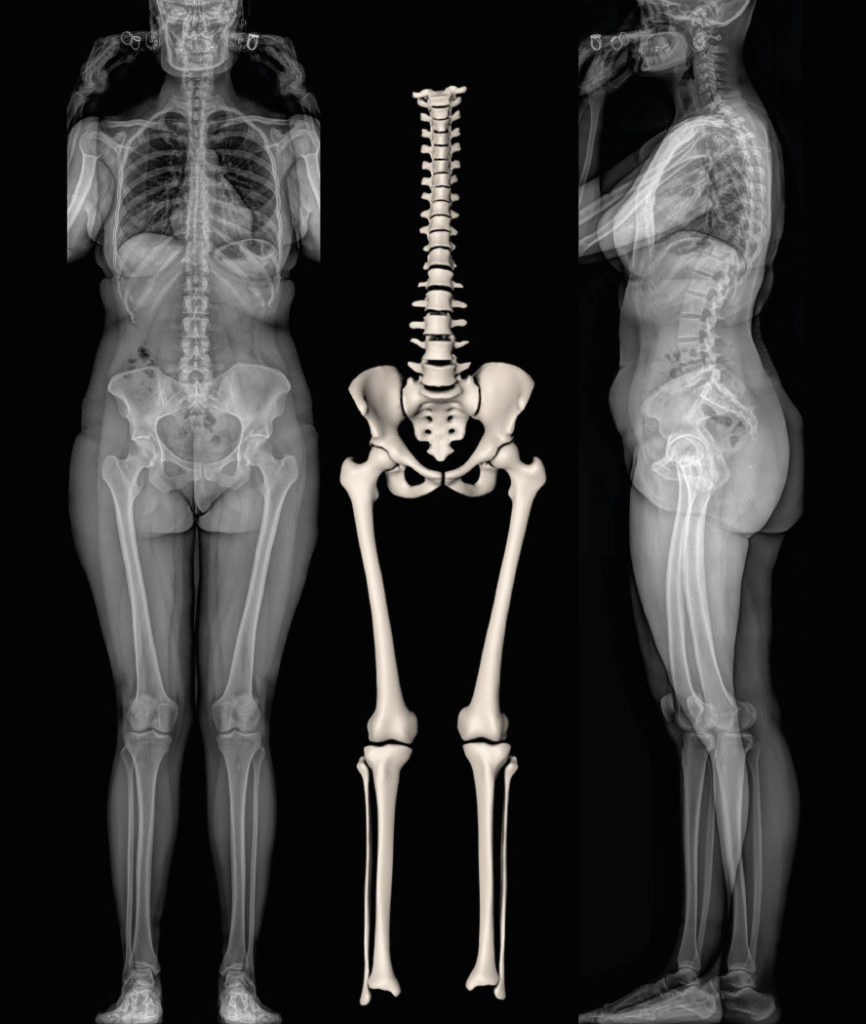

EOSedge – EOS imaging